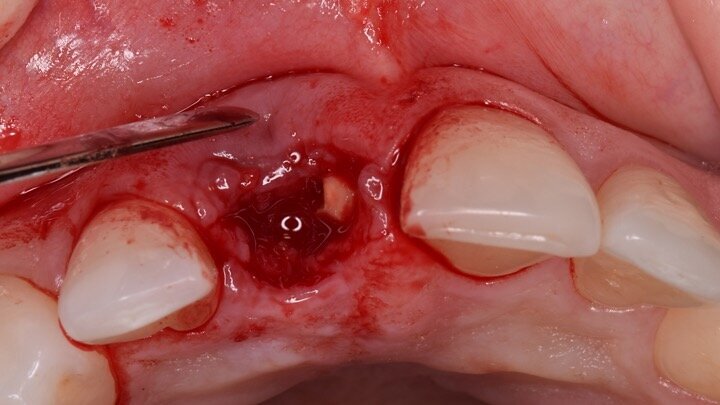

Figura 4. Exodoncia del diente.

Figura 5. Hundimiento de la zona estética anterior inmediatamente después de la extracción del diente por la reabsorción de la pared vestibular.